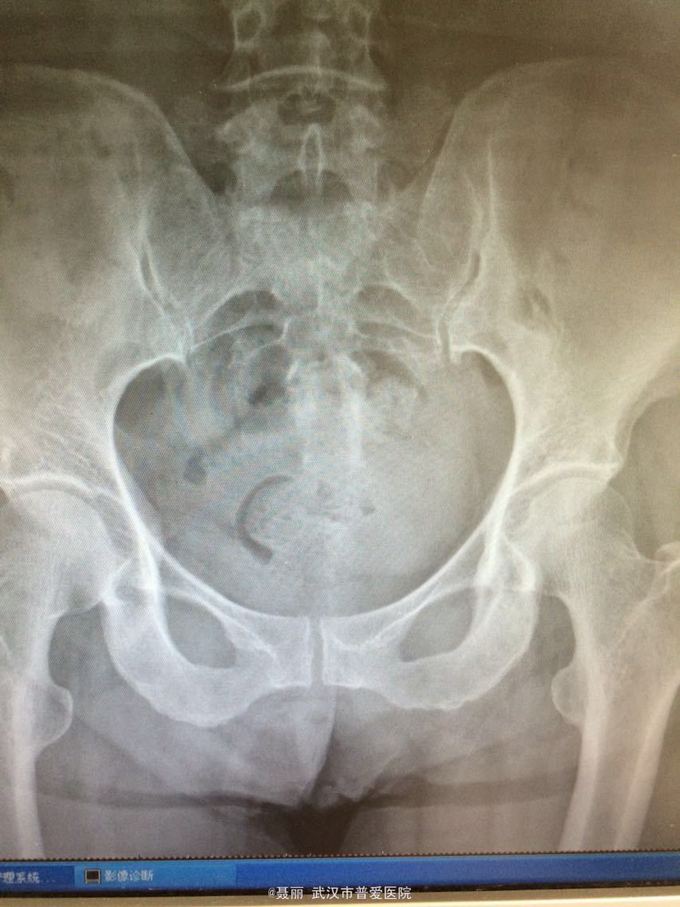

患者,女,61岁 因腰部疼痛,伴左下肢酸胀、疼痛、麻木5月余入院。 患者约5月前无明显外伤等诱因感腰腿疼痛不适,以腰部及左下肢为主,活动后左下肢疼痛加重,休息可缓解。 既往病史:既往体健,否认高血压、糖尿病等其他传染病史,否认食物药物过敏史。

辅助检查:2015年2月27号到我院拍腰椎MRI检查提示:L4椎体Ⅰ-Ⅱ度滑脱,腰椎退变。

初步诊断:腰椎滑脱症 治疗计划:1、完善相关检查:胸片、心电图,血常规,尿常规,肝肾功能电解质、术前全套 2,活血化瘀扩管治疗。卧床休息。 L4滑脱复位+L4/5椎间盘摘除、椎管减压+椎间cage3植骨融合术